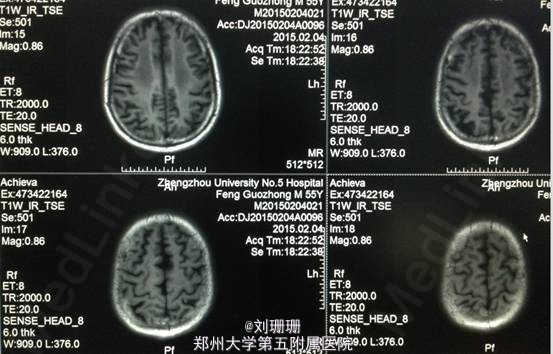

血压 120/80mmHg,神志清,精神一般,面部表情减少,构音清,言语顿挫欠流利,对答反应时间较长,查体欠合作。双侧额纹对称,双眼球各方向活动自如,无眼震,复视及视野缺损,双侧鼻唇沟对称,伸舌基本居中,咽反射灵敏。双上肢肌力Ⅴ级,双下肢肌力Ⅳ级,肌张力偏高无震颤,双侧腱反射对称,双侧巴氏征阴性。痛觉对称,共济运动因智能下降不能配合。双肺呼吸音粗,心率72次/分,律齐,双下肢无水肿。MMSE 18分。 头颅DWI提示双侧侧脑室旁对称性异常信号,结合病史符合一氧化碳中毒脑缺氧缺血所致的脑白质脱髓鞘。